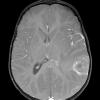

NEOPLASMS (EMBRYONAL)

ATRT - Atypical Teratoid Rhabdoid Tumor (11)